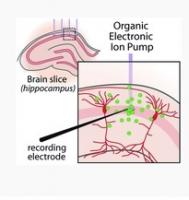

Actualité publiée le 13/09/2016ÉPILEPSIE: La pompe ionique qui éteint la crise au niveau du pixel neuronal

Actualité publiée le 25/08/2016